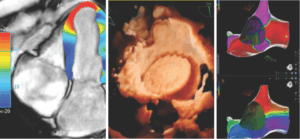

- Técnicas diagnósticas avanzadas como la ecocardiografía con strain longitudinal global, la resonancia magnética cardíaca y el eco estrés, que permiten detectar alteraciones tempranas en la función cardíaca.

- Sistemas de ablación 3D, que elevan la precisión en el tratamiento de arritmias.

- Imagenología avanzada con resonancia cardíaca, ecocardiografía strain, doppler y eco estrés.